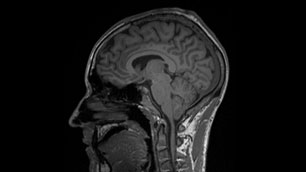

Brain cross section

The day was not yet over for the test subjects, even after the descent. They travelled by car for their first MRI at the German military base in Fürstenfeldbruck. The first test subject’s brain was scanned for 35 minutes at 19:30. The investigator was last into the tube, and his MRI was finally completed at 03:00. Only then could the first short night at sea level begin.

Even if a precise answer as to whether altitude sickness does indeed make the vascular walls permeable for fluids and protein molecules will not be available until after a detailed analysis of all collected data and samples, an initial glance at the MRI images and the study journals kept by the test subjects already appears promising. "The brain scans show smaller oedema in two participants. They are too small to cause the risky increase in cranial pressure, and hence are not dangerous. But they are clearly visible," says Limper. A trend is also apparent in the journals: test subjects noticed far more severe symptoms of altitude sickness in the morning – which is indicative of lower oxygen saturation levels in the blood during the early hours of the day. In contrast, many of the test subjects felt better in the evening.

The test subjects will be asked to give blood once more on 5 September. The 'afterwards' values, collected after their bodies have been allowed to 'breathe' for several days, will be used for comparison. The participants will complete another MRI examination in the middle of December: "We want to find out whether the oedema have disappeared completely."